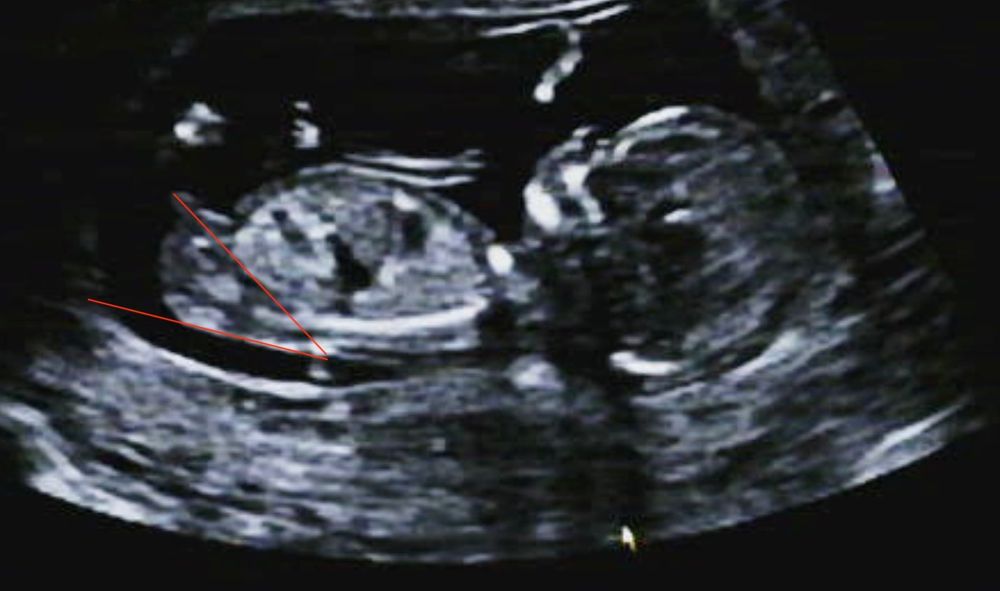

Угадываем пол по половому бугорку

30гр, пограничное состояние. С таким и девочка может быть.

СоФоЧкА , это первый попавшийся сайт с онлайн-транспортиром https://www.ginifab.com/feeds/angle_measurement/online_protractor.ru.php